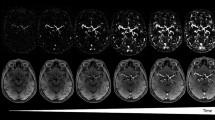

Fine vessel structures in head and thorax defined through 3D MR angiography

The enhancement effect of PAA-Gd on MR angiography contrast is first evaluated through 3D DCE MR angiography of the head and thorax of healthy mice, and the clinical Gd-DTPA contrast agent was adopted as control. As shown in upper panel of Fig. 2a and Supplementary videos 1 and 2, PAA-Gd can quickly distribute over each vascular branch accompanying with the bloodstream after the intravenous injection, and enhance the contrast of vessels evidently. More importantly, this angiography is still clearly visible without significant fading at 1 hour after injection, indicating that almost no PAA-Gd leaks out of blood vessels. Therefore, the PAA-Gd contrast agents can provide a suitable window period for the multiple complete DCE sequence scanning.

a Representative MR angiography obtained pre- and at different time points post-injection of PAA-Gd and Gd-DTPA. b Schematic drawing of vascular anatomy and the vascular identification in different directions of 3D angiography. Triplicates were performed independently with similar results. The embedded scale bar of frame a and b corresponded to 5 mm. Abbreviation: L/RSTV left/right superficial temporal vein, L/RPFV left/right posterior facial vein, L/RAFV left/right anterior facial vein, L/RECA left/right external carotid artery, L/RICA left/right internal carotid artery, L/RCCA left/right common carotid artery, L/REJV left/right external jugular vein, VA vertebral artery, L/RSA left/right subclavian artery, L/RSV left/right subclavian vein, BCT brachiocephalic trunk, AOAR, aortic arch, ITV internal thoracic vein, L/RPA left/right pulmonary artery, RPV right pulmonary vein, IVC inferior vena cava, HV hepatic vein, HPV hepatic portal vein, L/RA left/right atrium, L/RV left/right ventricle.

In comparison with PAA-Gd, the blood vessel distributions of mice treated with Gd-DTPA were barely visible, whereas only the contrast of liver parenchyma increased significantly with time (lower panel of Fig. 2a, Supplementary video 3 and 4), indicating Gd-DTPA extravasates from hepatic blood vessels rapidly after injection, and distributed in the extracellular space, especially distributes in liver, leading to difficulty in characterizing the structure of vascular system. For quantitatively evaluating the performance of these two contrast agents, the temporal evolution of the average relative T1 MRI signal intensities of vessels and hepatic parenchymal region were analyzed (Figs. S5 and S6). The quantitative analysis results further support that PAA-Gd has long temporal window of MR angiography scanning and negligible diffusion out of the liver vessels, endowing PAA-Gd with the ability to largely enhance the spatiotemporal resolution of MR angiography.

Based on the vascular anatomic atlases of mice, the fine vessel structures of mouse in the probe-enhanced MR angiography are carefully identified. The schematic drawing of blood vessels and the 3D angiography results in different directions were given in the left and right panels of Fig. 2b. Accordingly, a great range of blood vessels can be observed clearly in the angiography, including main arteries, veins, and even tiny vessels with submillimeter diameter. Every clinically important vessel, especially the vessels of cardiovascular systems, such as aortic arch (AOAR), common carotid artery (CCA), subclavian artery/vein (SA/V), and even vertebral artery (VA), can be readily identified. In addition, although the heart of mouse beats very fast (400–600 times/min37), four main cardiac chambers can also be clearly distinguished (the red dotted line of demarcation), highlighting the excellent spatial resolution of MR angiography enhanced by PAA-Gd. Therefore, PAA-Gd contrast agents undoubtedly brings a qualitative leap to MR angiography, especially for the cardiovascular angiography.